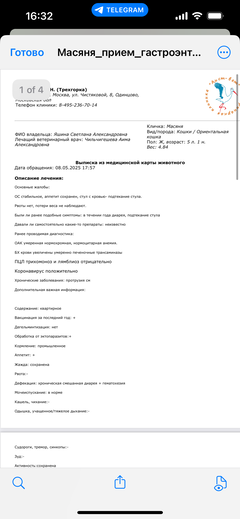

Была куплена в питомнике взрослой. У Масяни начались проблемы с кишечником и она стала подтекать и все пачкать. Надо отдать должное хозяевам - ее обследовали вдоль и поперек - как говорили местные врачи, сдавали много анализов но диагноза так и не поставили.

И проблема никуда не ушла 😔

Забрали. Оказалось, что у малышки постоянно болит спина...

Ярко выраженная болезненность в области крестца, на обезболе полегче. По результатам приема невролога проведена миелография - множественная компрессия, возможно опухоль, возможно грыжа, нужно удалять...